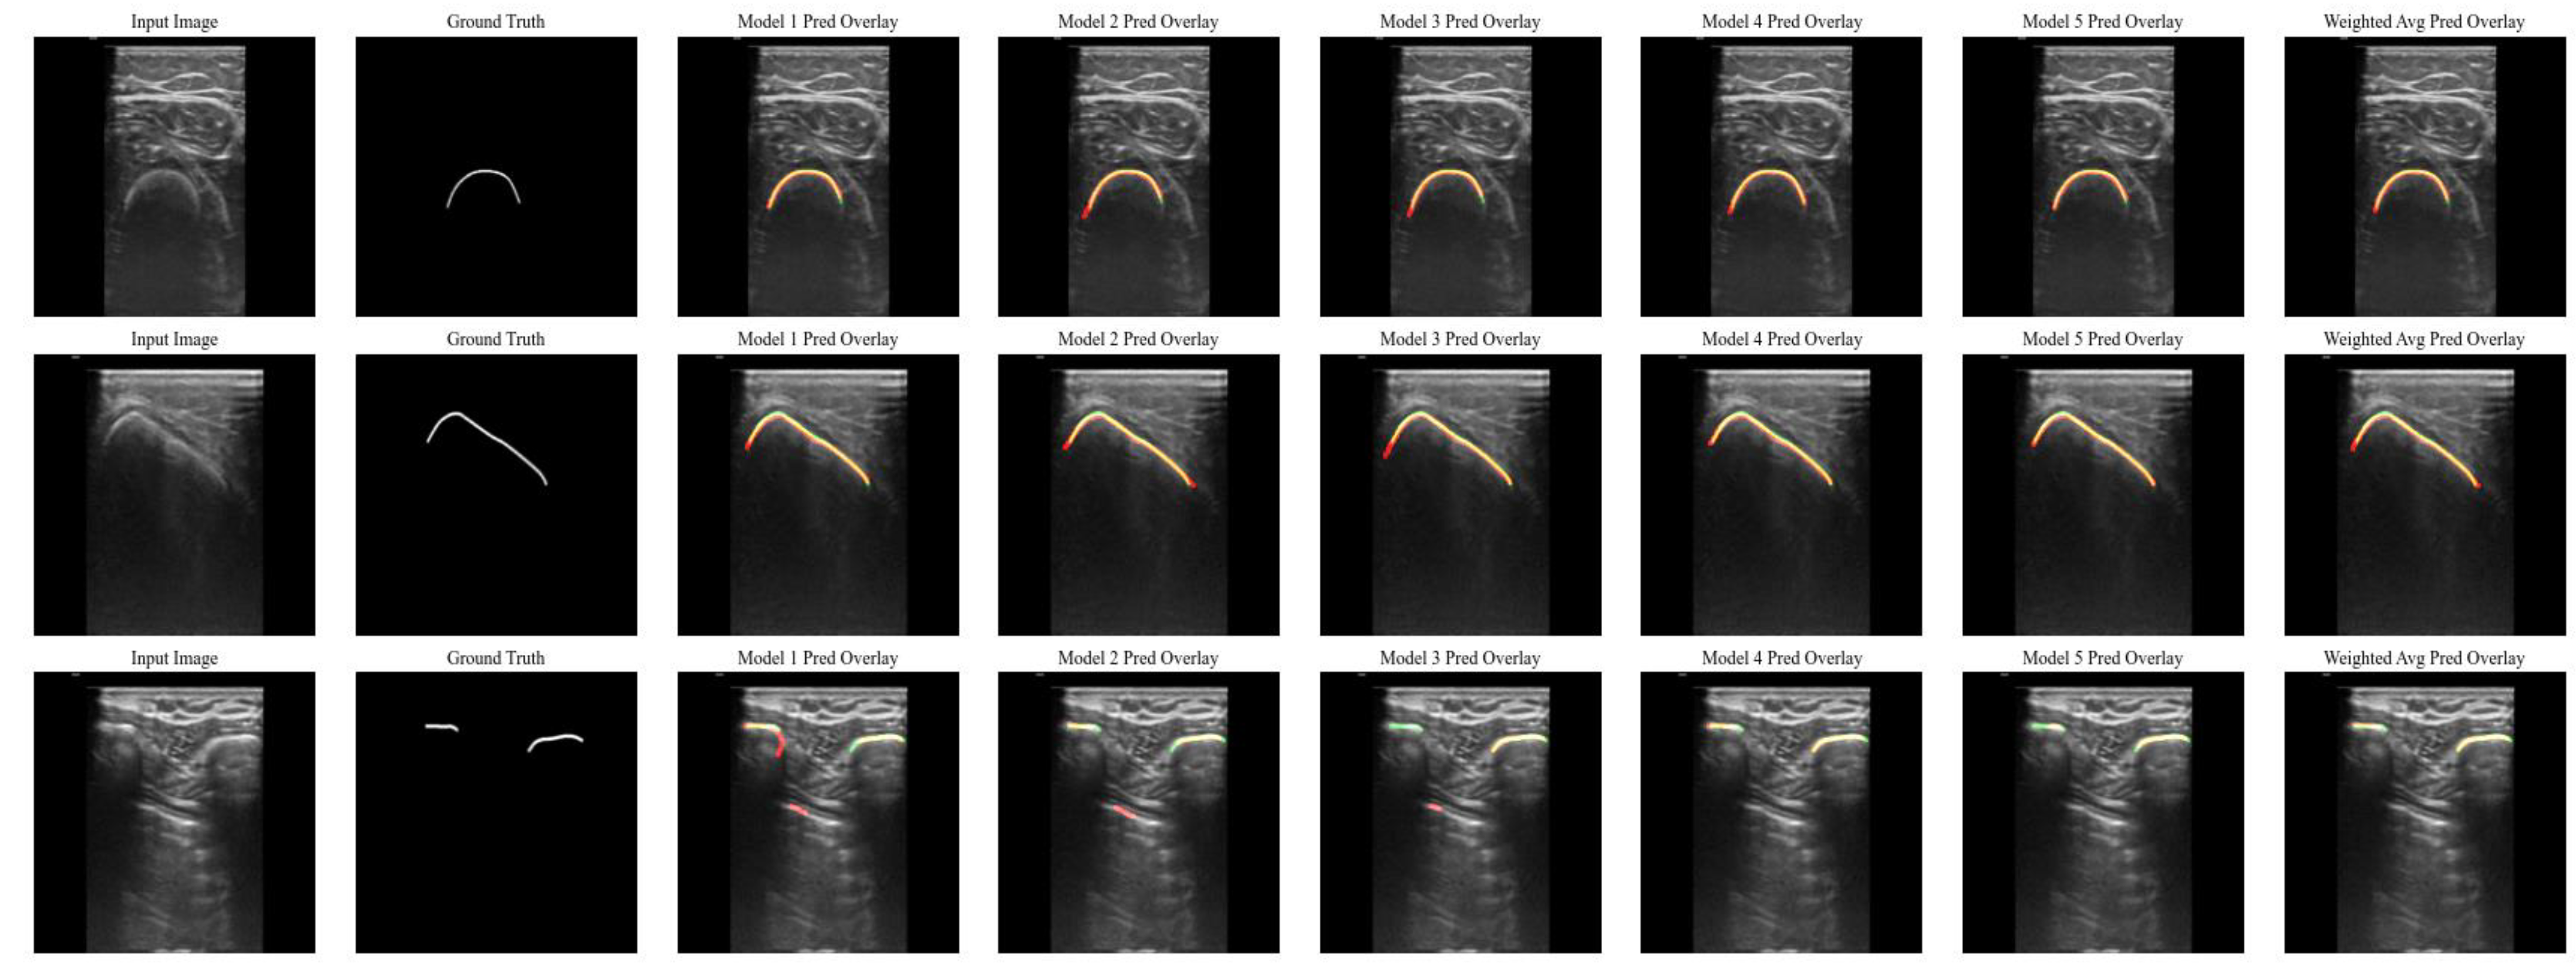

3. Results